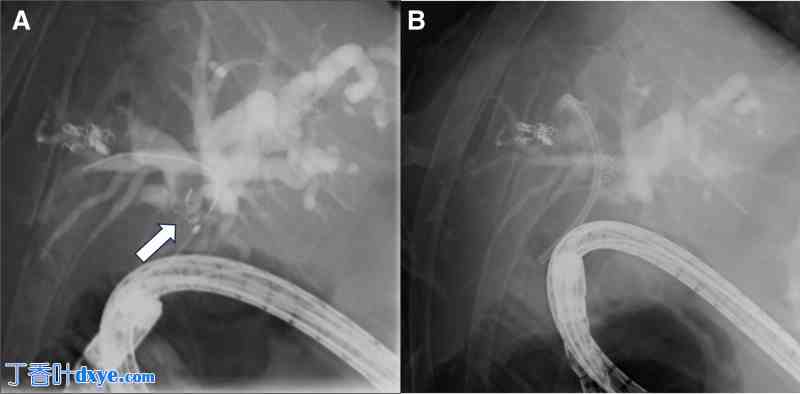

住院期间,增强 CT 显示用于栓塞 A8 肝动脉的线圈的一部分已移位到肝门 (图 2A)。此外,还观察到肝内胆管扩张 (图 2B)。

图 2。

2 年前动脉瘤线圈栓塞后进行的 CT 扫描与入院时的 CT 扫描对比。 (A) 2 年前胆道重建手术后,肝动脉 (A8) 动脉瘤线圈栓塞后进行的 CT 扫描。 (B) 入院时的 CT 扫描显示线圈部分移位至肝门 (➡),同时肝内胆管扩张 (▲)。 CT = 计算机断层扫描。